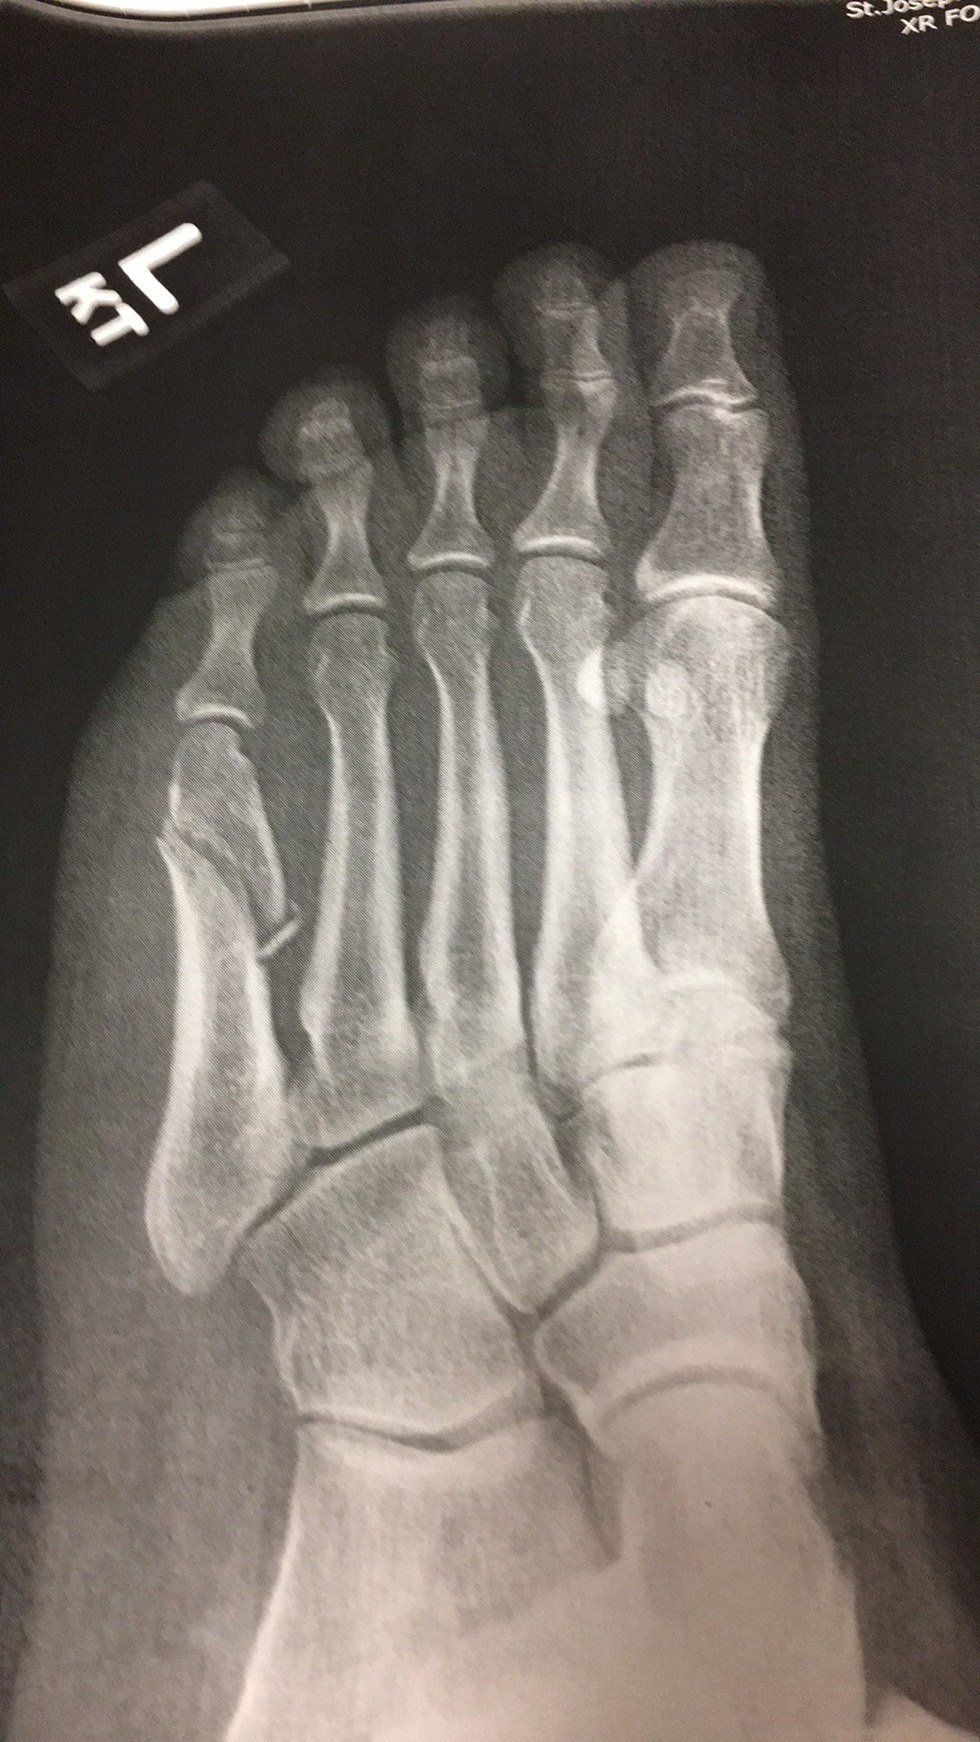

I’m part Native American; mostly Blackfeet, but also part Athabaskan. Lately I’ve been trying to connect more with my culture, and there were some YouTube videos of Blackfeet dancers doing fancy dancing (which is what I always wanted to do). So, I watched them, and tried to emulate them. What I didn’t realize was how hard the footwork actually is. It’s so hard that instead of landing on my foot the right way, I landed on it sideways with my full weight, and it rolled under me. What happened next is the lovely picture you see above. I almost laughed when my mom asked me, after I told her I had tried dancing, if I had tried fancy dancing. I guess that is the style that engenders the most risk.

The doctor gave me a walking boot, and I had to buy crutches, but I can’t put weight on the front part of my foot – which sucks, because I put the most weight on the balls of my feet. It’s funny how something isn’t that big of a deal until it happens to you. I’ve seen friends and family members struggle with foot injuries before, and while I did everything to help them at the time, it didn’t occur to me how difficult getting around like this actually is. I’m overweight, which helps absolutely nothing, and I’m having a lot of pain in my right foot from the strain of putting almost all of my weight on it. And I had problems with my feet before this happened.